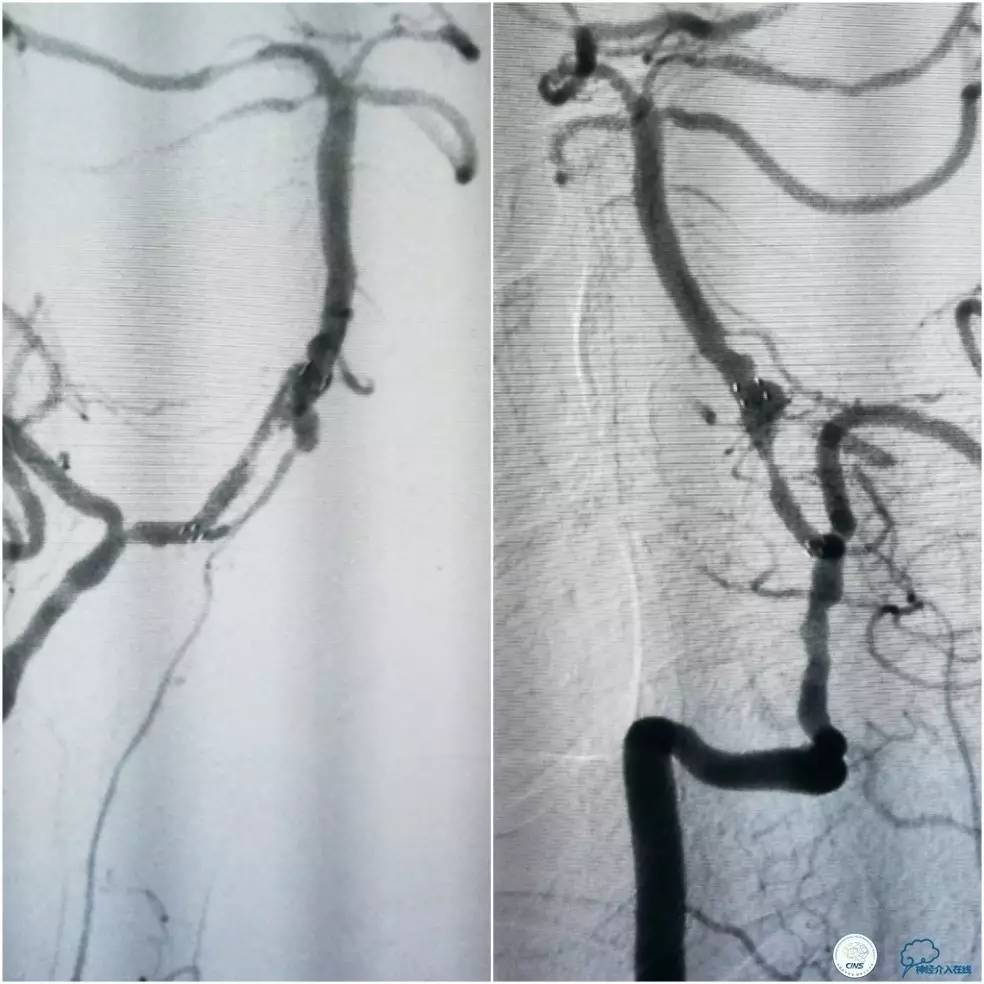

其后造影显示支架贴壁良好,远端血管显影好,前向血流TICI3级(图16)。

图16

缓慢回撤6F导引导管至锁骨下动脉,造影显示右椎V1段支架无移位,前向血流正常(图17)。

图17